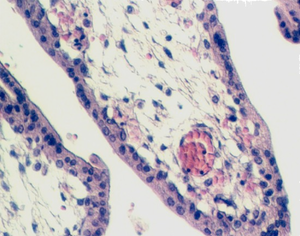

Look at the side of the chorionic plate facing the uterus and look for stem villi originating from the chorionic plate.  They are filled with mesenchyme and lined by the two layers of trophoblast cells. The inner layer, the cytotrophoblast, divides and gives rise to the outer layer, the syncytiotrophoblast.  This is a multinucleated cellular layer that covers the surface of the villi.

placenta_young3.jpg (74339 bytes)placenta_young4.jpg (111706 bytes)